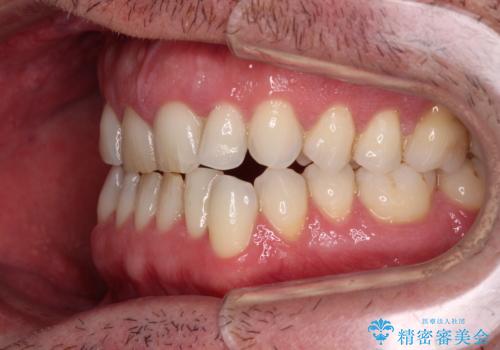

- 前歯でものを噛みきりたいとのことで来院された患者様です。

以前矯正治療を経験されたそうですが、舌の突出癖により上下前歯に隙間ができている様子でした。

前歯の非接触改善は、インビザラインの得意とするところですが、マウスピース矯正は絶対に継続できないとのことで、ワイヤー装置にて矯正治療を行うこととしました。